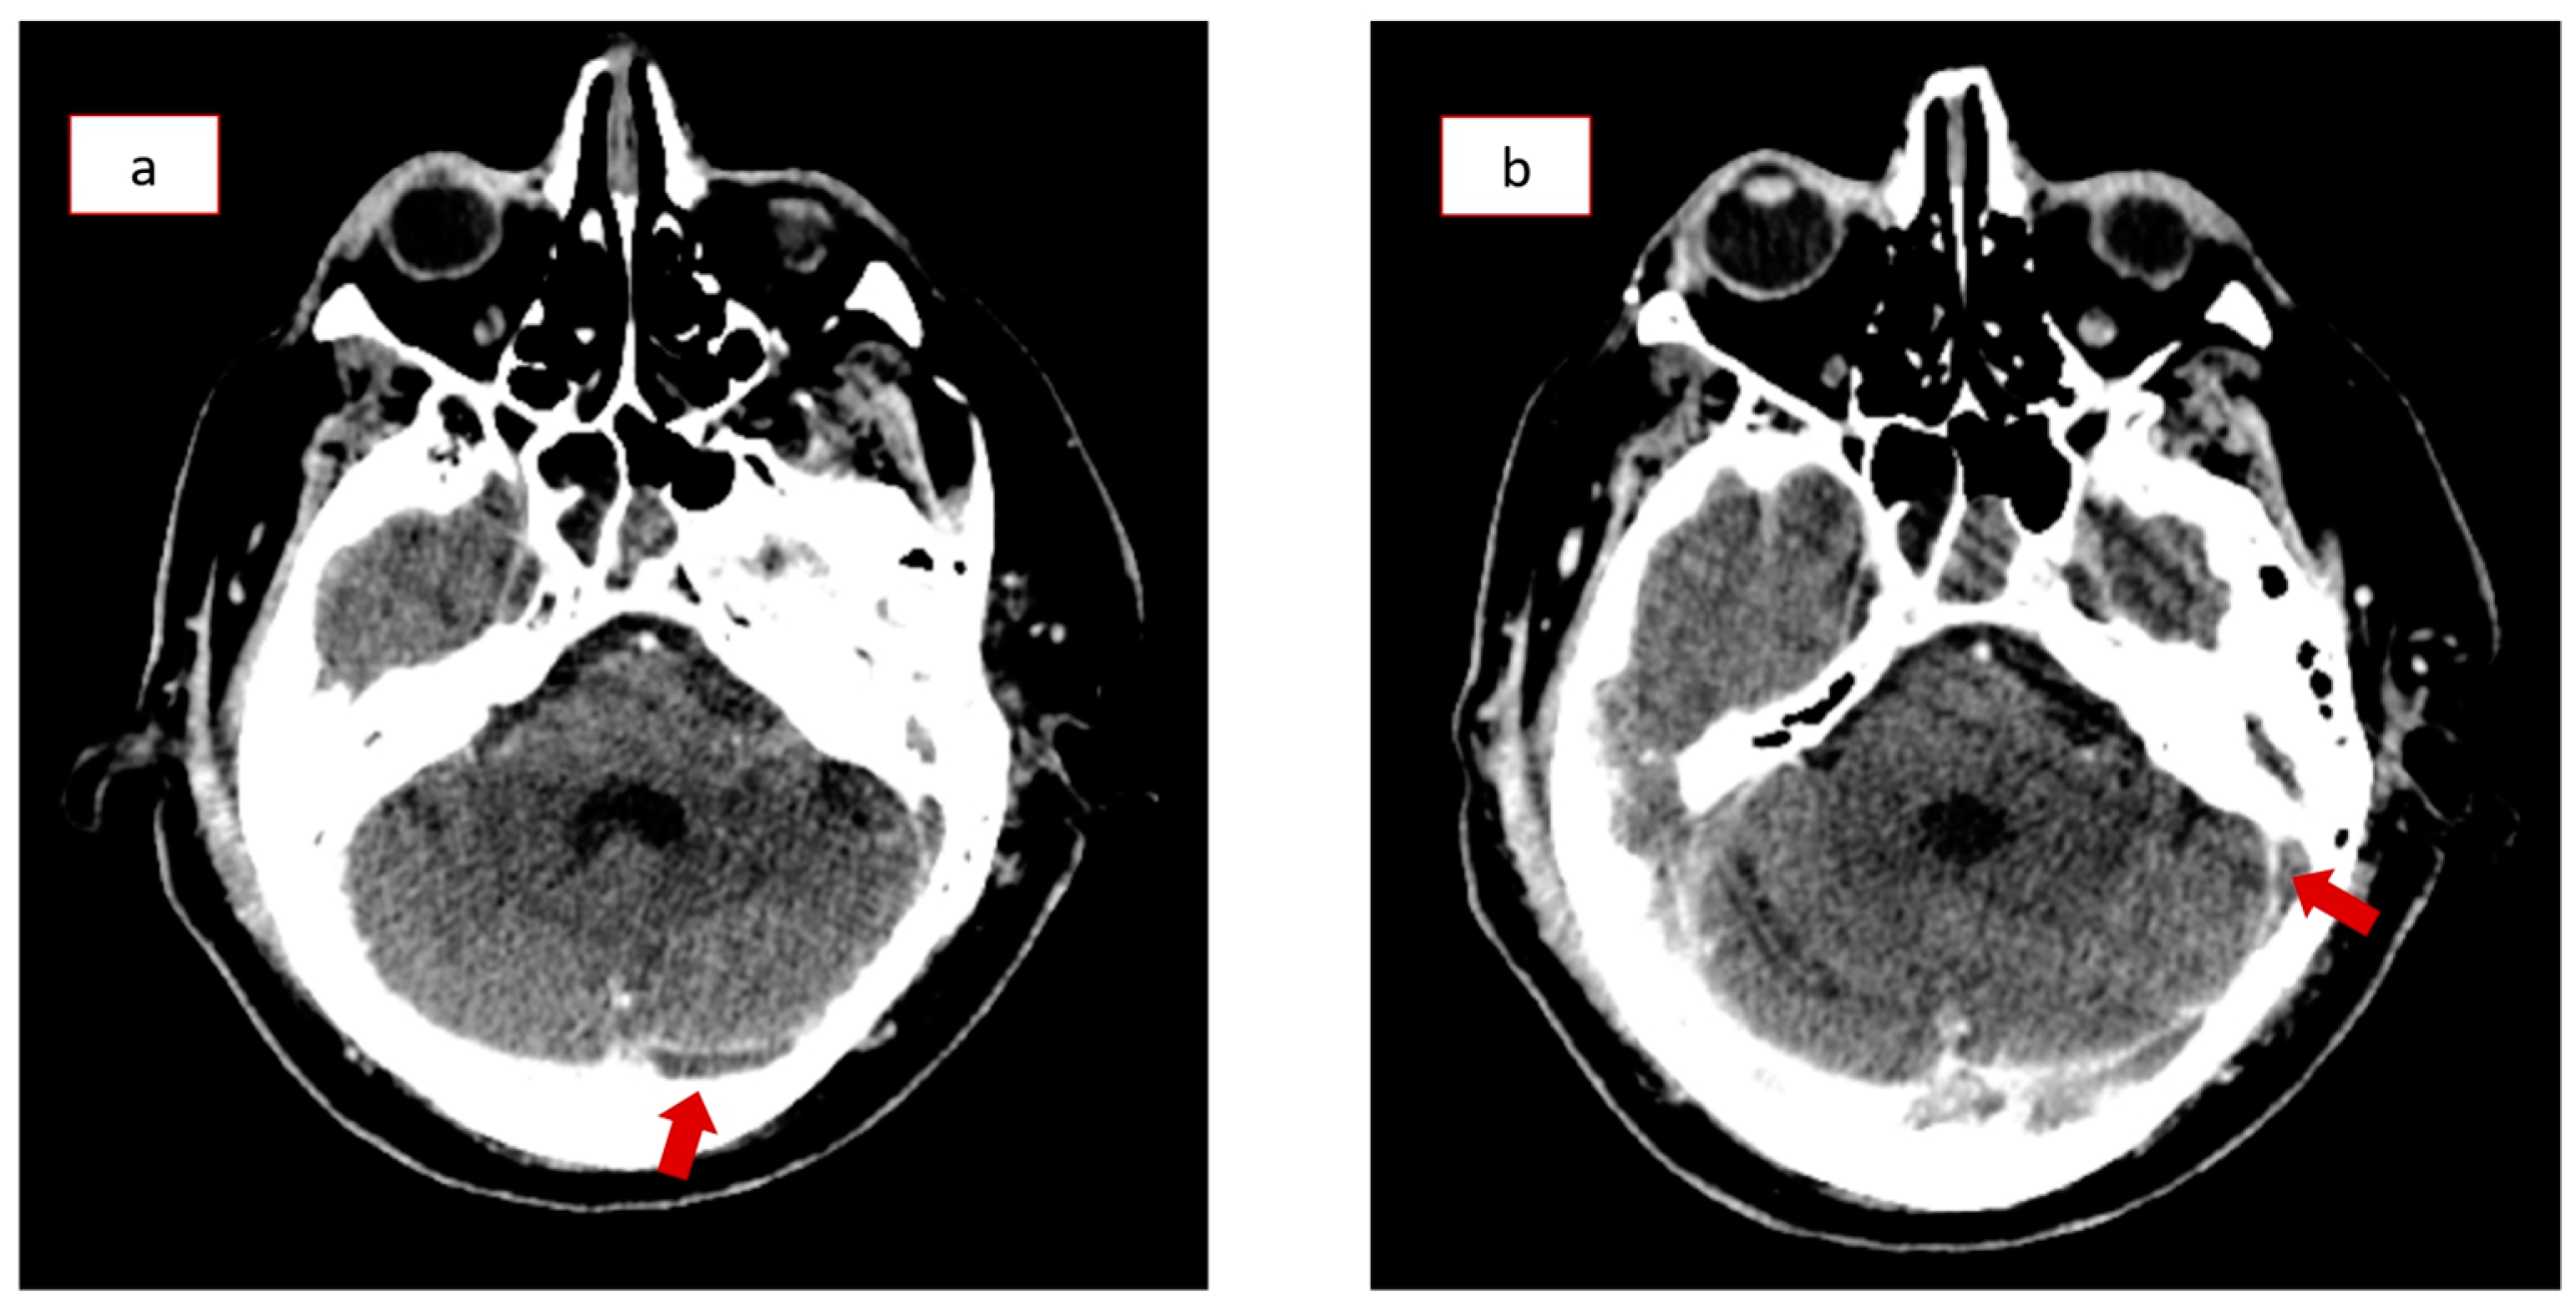

During his stay in the ICU, the patient also developed a cerebrospinal fluid (CSF) infection, which was successfully treated with broad-spectrum antibiotics. Despite his worsening clinical condition, the following series of brain CT scans showed continuous improvement of the initial traumatic hemorrhagic findings. The mismatch between his clinical and imaging findings raised suspicion for post-traumatic cerebral venous thrombosis, so the patient underwent a CT venography (CTV) on the 14th day of hospitalization. The CTV revealed left transverse sinus and sigmoid sinus thrombosis (Figure 2a,b), which were treated with anticoagulation therapy (high-dose enoxaparin) according to appropriate protocols (Supplementary Figure S1). The patient underwent a tracheostomy due to prolonged mechanical ventilation, and he was then transferred to the Neurosurgical Department, where a gradual neurological improvement was recorded (GCS of 14/15). He was discharged after thirty-eight days of hospitalization with only minor neurological deficits. The patient presented again with cerebrospinal fluid (CSF) rhinorrhea 36 days after discharge, while new CT scans indicated a bone lesion in the roof of the right ethmoid sinus, necessitating lumbar drain catheter insertion with a continuous flow target of 7–10 mL CSF per hour. He was finally discharged after nine days, and no other complications occurred during his following regular follow-ups.

Figure 2.

Computed tomography venography (CTV) on the 14th day in the Intensive Care Unit (ICU) revealing thromboses in the (a) left transverse and (b) sigmoid sinus (red arrows).